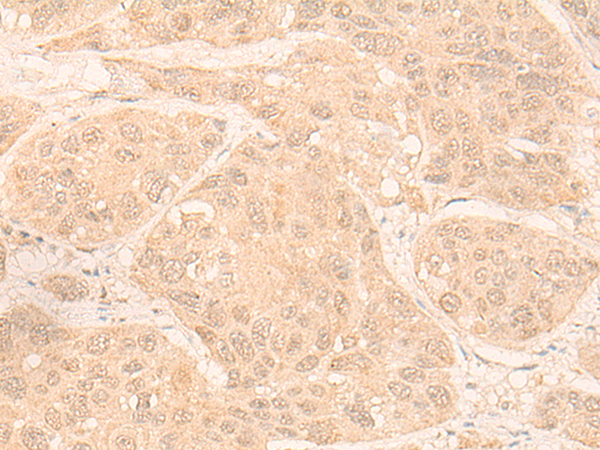

分类: 科研抗体货号: P13239别名:应用: IHC反应种属: Human